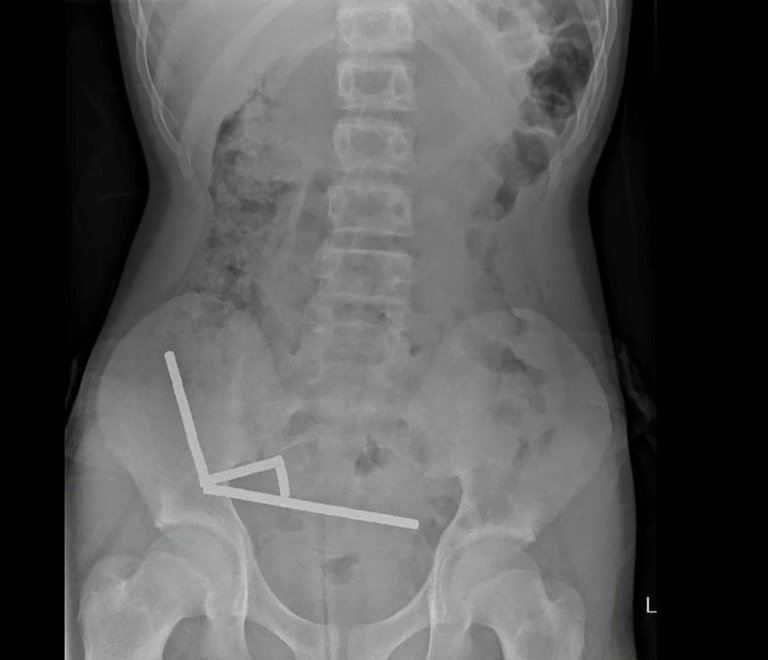

Surgeons at Tauranga Hospital in New Zealand recently performed a complex operation on a 13-year-old boy who swallowed between 80 to 100 high-power magnets. The magnets, which the boy purchased through the online shopping platform Temu, caused significant health complications, including tissue death in his intestines.

The incident came to light after the boy experienced four days of severe abdominal pain. According to a report in the New Zealand Medical Journal, the child disclosed that he ingested the magnets approximately one week prior to his hospital visit. These neodymium magnets, measuring 5x2mm, have been banned in New Zealand since January 2013.

Doctors found that the magnets had clumped together in four straight lines within the boy’s intestines, leading to necrosis—tissue death—affecting four areas of his small bowel and caecum, which is part of the large intestine. The surgical team had to remove the dead tissue along with the magnets during the operation, though the specific date of the procedure was not disclosed. After an eight-day recovery period in the hospital, the child was able to return home.